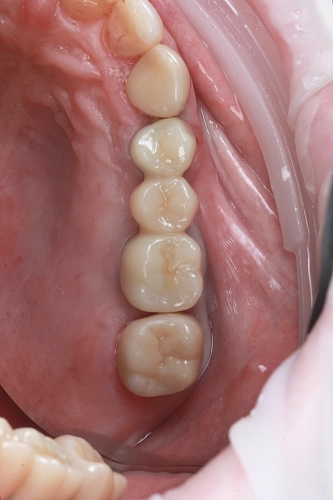

На фото проведена комплексная имплантация двух жевательных зубов стоматологом -хирургом Федотовым Р.В.